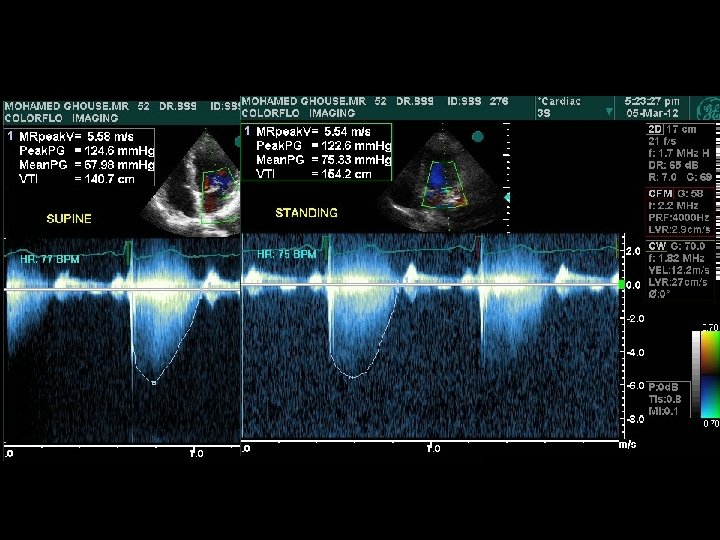

Abrupt standing • S 2 split which may be wide, may narrow down , while the fixed split may persist • A 2 OS interval widens – differentiates from wide split of S 2 • All murmurs ( except MVP/HOCM) decrease • ESM of HOCM becomes louder and longer • Click occurs earlier, murmur becomes longer in MVP – loudness shows variable response